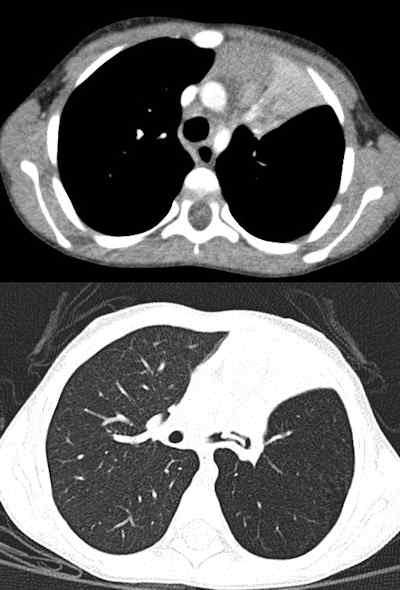

![Chest CT of 8-day-old girl with respiratory distress (80 kV, 51 average effective mAs, CTDIvol = 2.3 mGy, DLP [dose length product] = 33 mGy cm, E[effective dose] = 1.1 mSv. CT was performed to exclude congenital lung abnormalities because of family history and small volume lungs. Image shows ground glass opacity and septal lines consistent with respiratory distress syndrome. In all four figures, CTDIvol and DLP are expressed in terms of the 16 cm CT dosimetry phantom; these should be divided by approximately two to be expressed in terms of the 32 cm CT dosimetry phantom. Effective dose was calculated from DLP using conversion coefficients specific to this scanner and using the International Commission on Radiological Protection Publication 103 definition of effective dose. All images courtesy of Zoe Brady, PhD.](https://img.auntminnieeurope.com/files/base/smg/all/image/2012/08/ame.2012_08_15_08_57_30_715_2012_08_15_pediatrict_CT_pic1.png?auto=format%2Ccompress&fit=max&q=70&w=400)

The researchers compared average dose values at the Royal Children's Hospital (RCH) in Melbourne with international DRLs for common pediatric CT examinations. They found the use of 80 kV for both chest and abdomen/pelvis imaging in children younger than 5 years old leads to a significant dose saving, but conceded there is potential for dose optimization by reducing scan lengths for body examinations for children older than 5 years old. The plan now is to review these protocols to determine whether there is appropriate justification for the extended scan lengths.

Furthermore, the reference mAs values for chest imaging must be justified, particularly relative to the abdomen/pelvis examination values for the same age groups, according to Brady. Because of the inherent contrast in the chest and lack of attenuating tissue, it was expected that these values might be lower for chest examinations than for abdomen/pelvis examinations, but in fact in the older age group they were found to be higher.